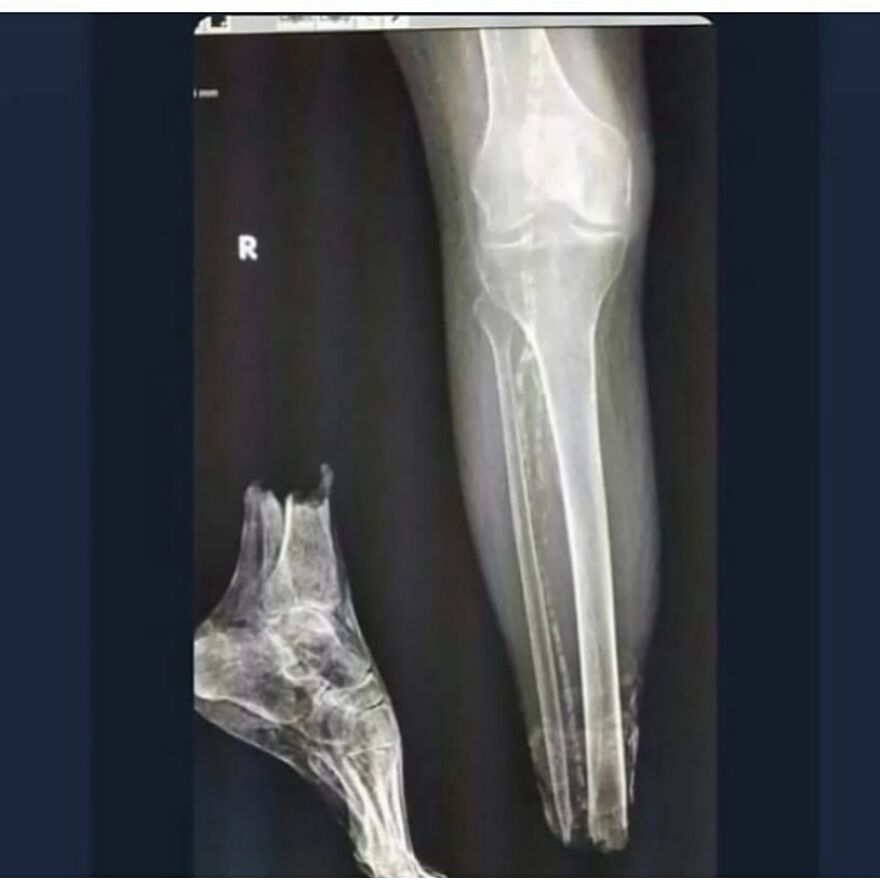

A dodgeball injury that resulted in radius and ulnar shaft fracture, aka broken forearm!

This sustained dodgeball injury has led to a bilateral diaphyseal fracture involving both the radius and ulnar shaft, thereby presenting as a fracture of the forearm.

This particular injury entails the disruptive discontinuity of the long bones situated within the antebrachial region, namely the radius and ulnar diaphyses.